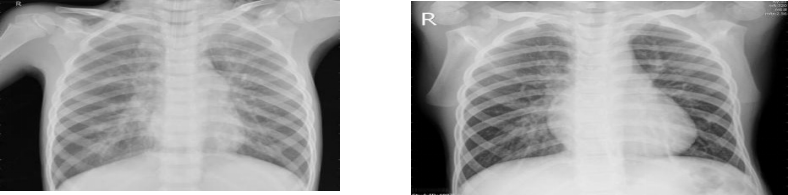

Research on an Intelligent Pneumonia Diagnosis Model Based on Improved Convolutional Neural Networks Using Chest X-ray Images

Pneumonia, a common health concern today, requires early and accurate diagnosis. Chest X-ray examinations play a critical role in the early detection of pneumonia. To enhance diagnostic accuracy, this study utilizes a deep learning-based convolutional neural network (CNN) model, trained on a dataset of 5,216 chest X-ray images obtained from pediatric patients aged 1-5 years at Guangzhou Women and Children's Medical Center. Among these, 3,875 images show signs of pneumonia and 1,341 images are normal, serving as the training and testing data for the model. By incorporating Dropout techniques and Batch Normalization methods, the model’s robustness and generalization ability were significantly improved. Experimental results demonstrate that the model achieves a diagnostic accuracy of 97.83%, which will effectively alleviate physicians’ workload and holds substantial clinical application value.